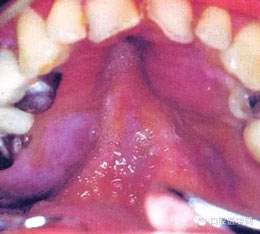

(六) Kaposi肉瘤: 主要發(fā)生于軟、硬腭粘膜。

(七)非霍奇金淋巴瘤: 多位于牙齦或腭粘膜。